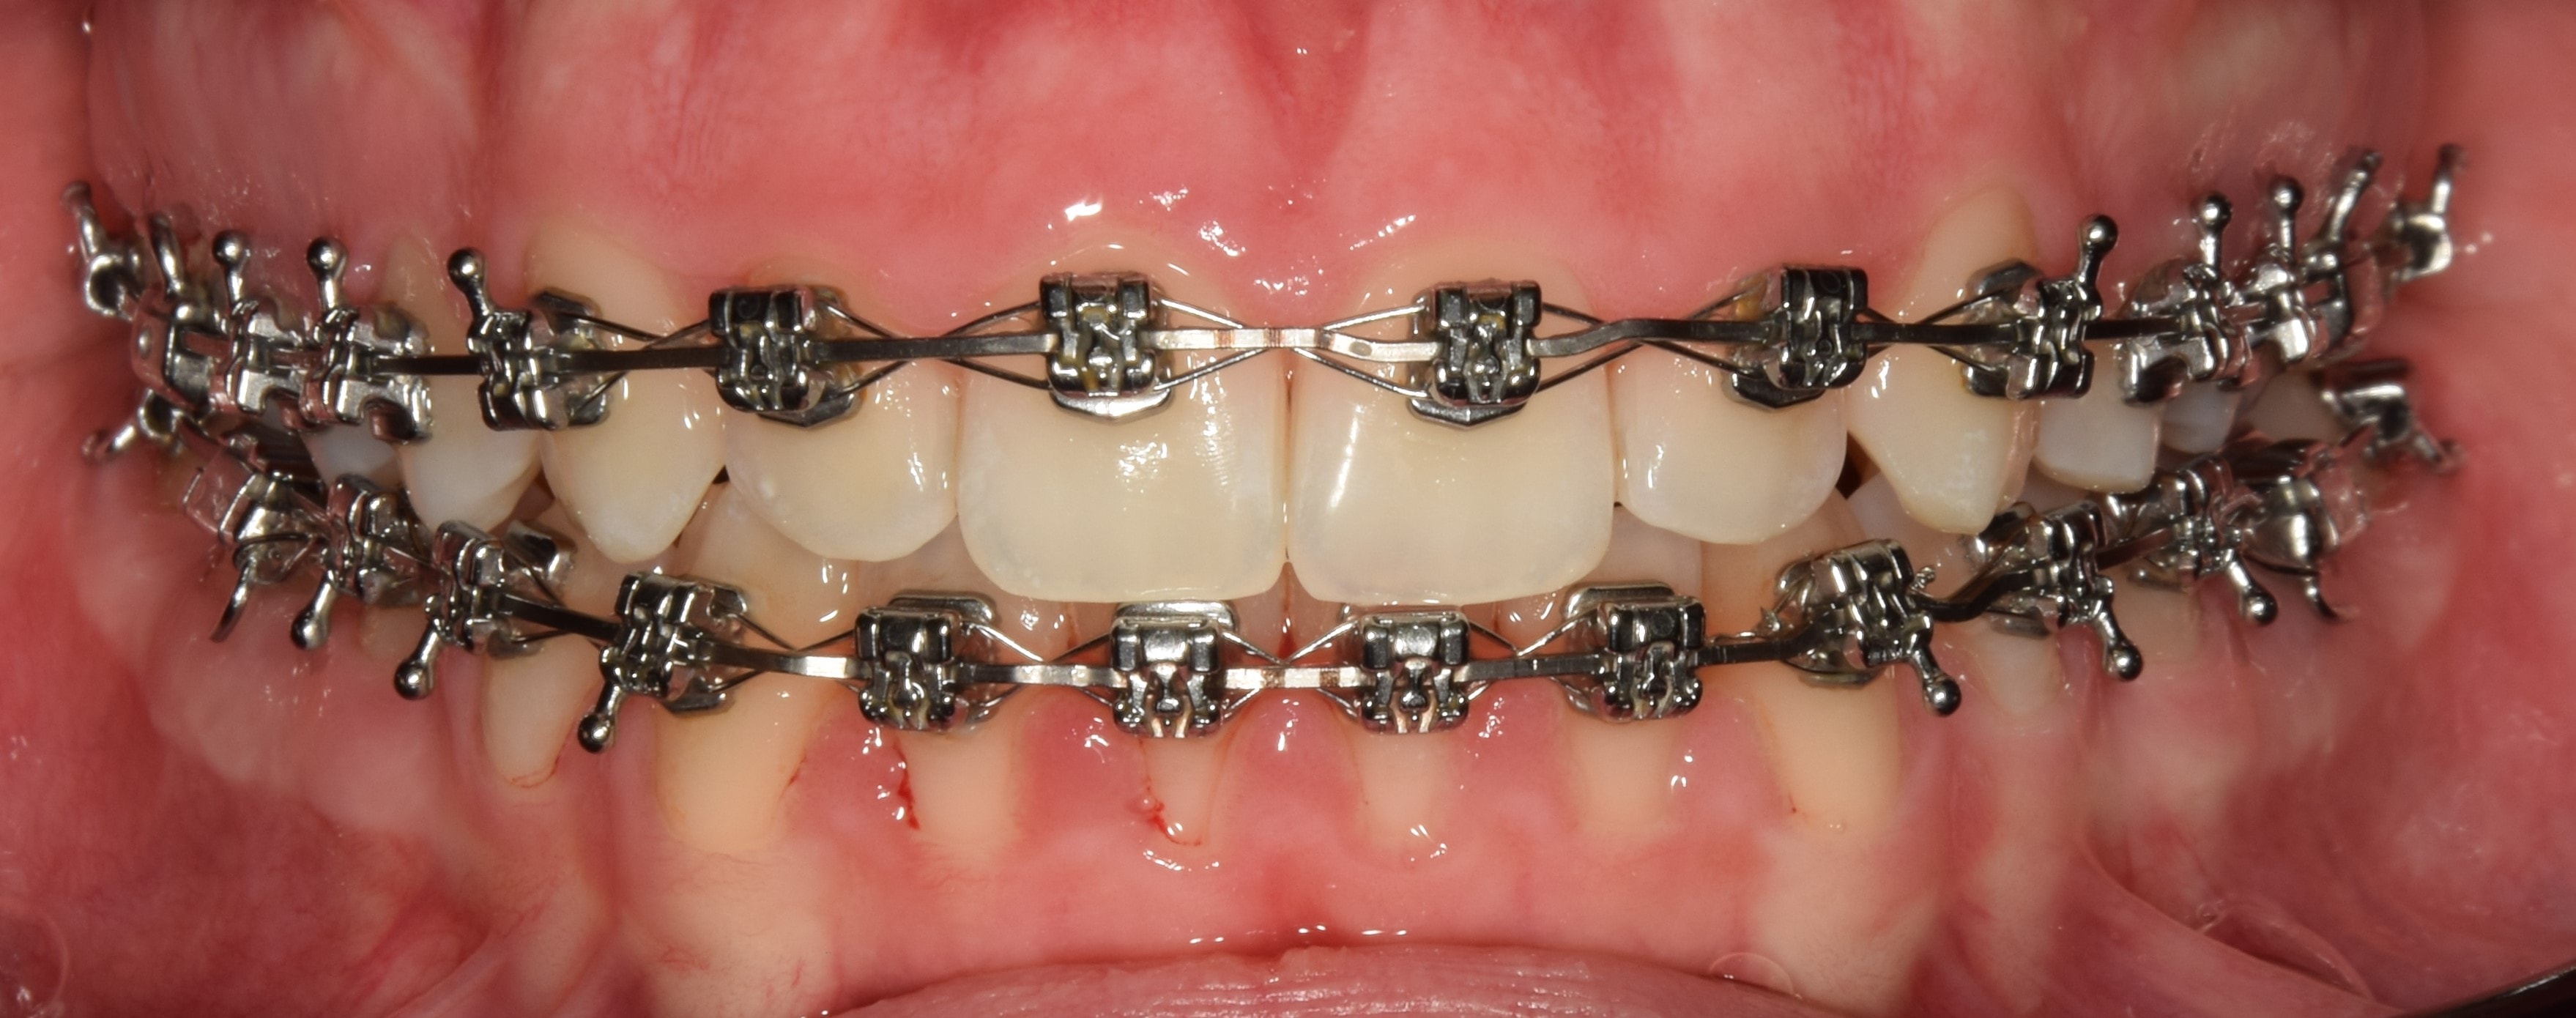

Harapásemelő

Harapásemelők alatt a fogak rágó (oldalsó fogaknál), vagy belső (elülső fogaknál) felszínre ragasztott, színes tömőanyagból készült blokkokat értjük. Ezeknek köszönhetően eltávolodik egymástól az alsó felső fogív, és mivel a fogak nem érintkeznek egymással, gyorsabb és fájdalommentesebb a fogmozgatás. További nagy előnyük, hogy mivel az alsó-felső fogív a kezelés elején csak a harapásemelőkön érintkezik egymással, így a bracketekre nem lehet ráharapni, azok nem esnek le. Segítségünkre vannak mind a nyitott-, mind a mélyharapás kezelésében. Minden kezelésemnél használok harapásemelőt. Eltávolításuk speciális fúrókkal történik, így a fogzománcot nem sértjük meg.